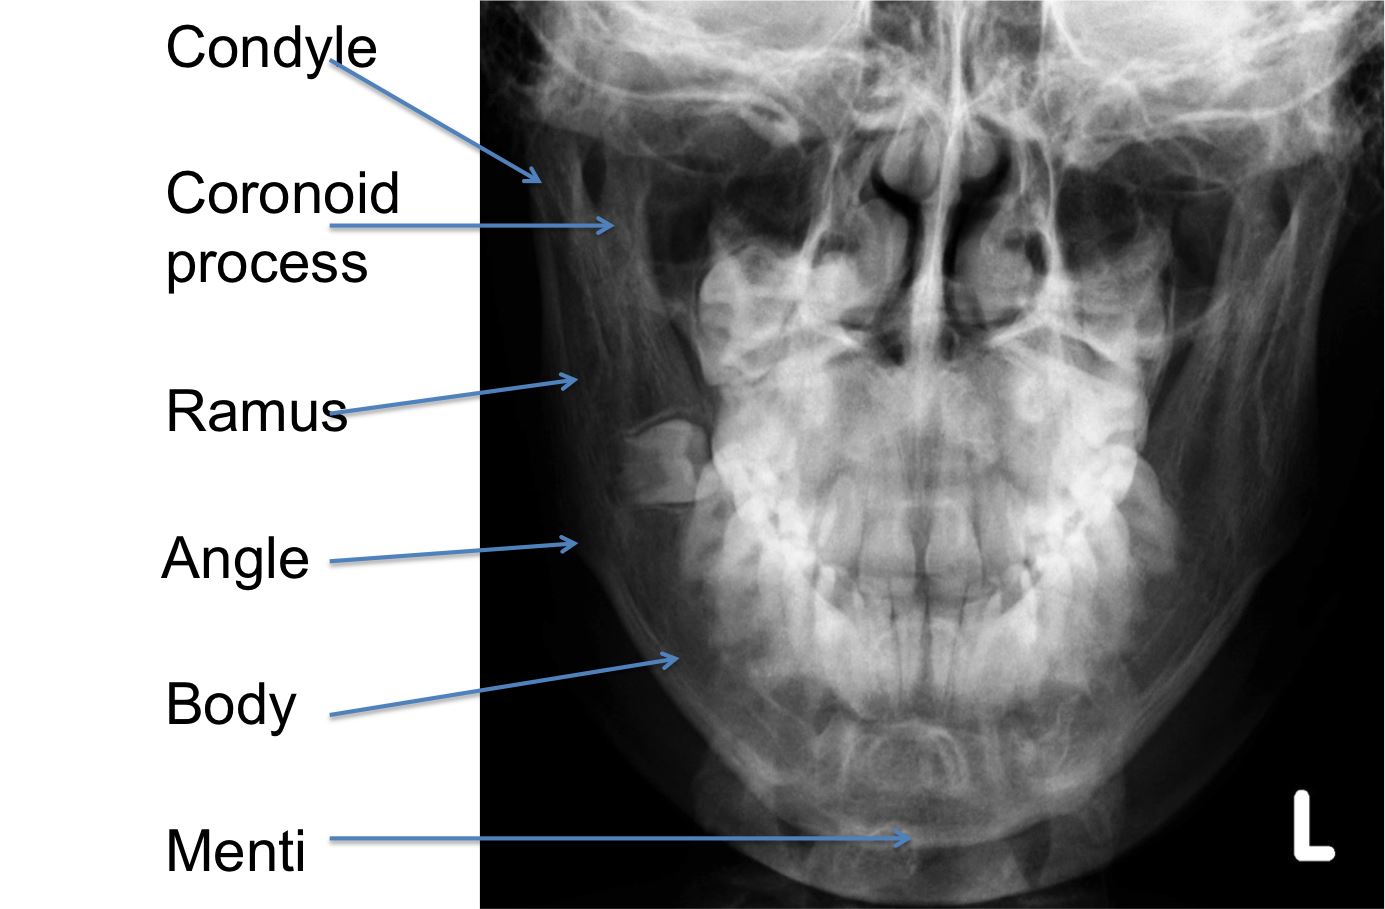

PA for Mandible

Part Position: Forehead and nose on IR; OML perpendicular to IR.

Central Ray: Perpendicular to exit the acanthion.

Collimation: 6×8 l/w

PA Axial for Mandible

Part Position: Forehead and nose on IR; OML perpendicular to IR.

Central Ray: 20-25° cephalad, exiting at acanthion.

Collimation: 6×8 l/w